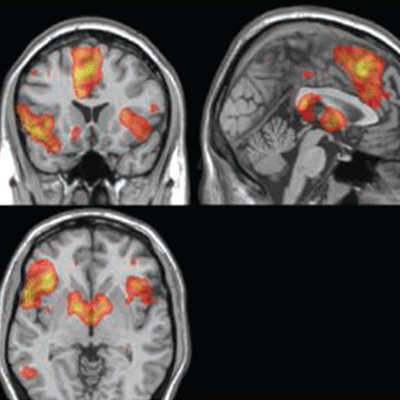

Recuerda la empresa Cephos, una de las dos que en Estados Unidos más activamente promocionan el uso de la resonancia magnética funcional para "saber la verdad" (la otra es No Lie MRI), que ya hay 30 artículos científicos publicados sobre los cambios detectables en el flujo sanguíneo cerebral cuando se miente o se piensa deshonestamente. Uno de ellos, publicado el año pasado, se titula: Patrones de actividad neuronal asociados a decisiones morales honestas y deshonestas, y el título de otro empieza: La verdad sobre la mentira. El desacreditado polígrafo está dando paso a otra técnica más avanzada, con mayores posibilidades de leer el pensamiento.

Los experimentos han hallado la firma cerebral del engaño